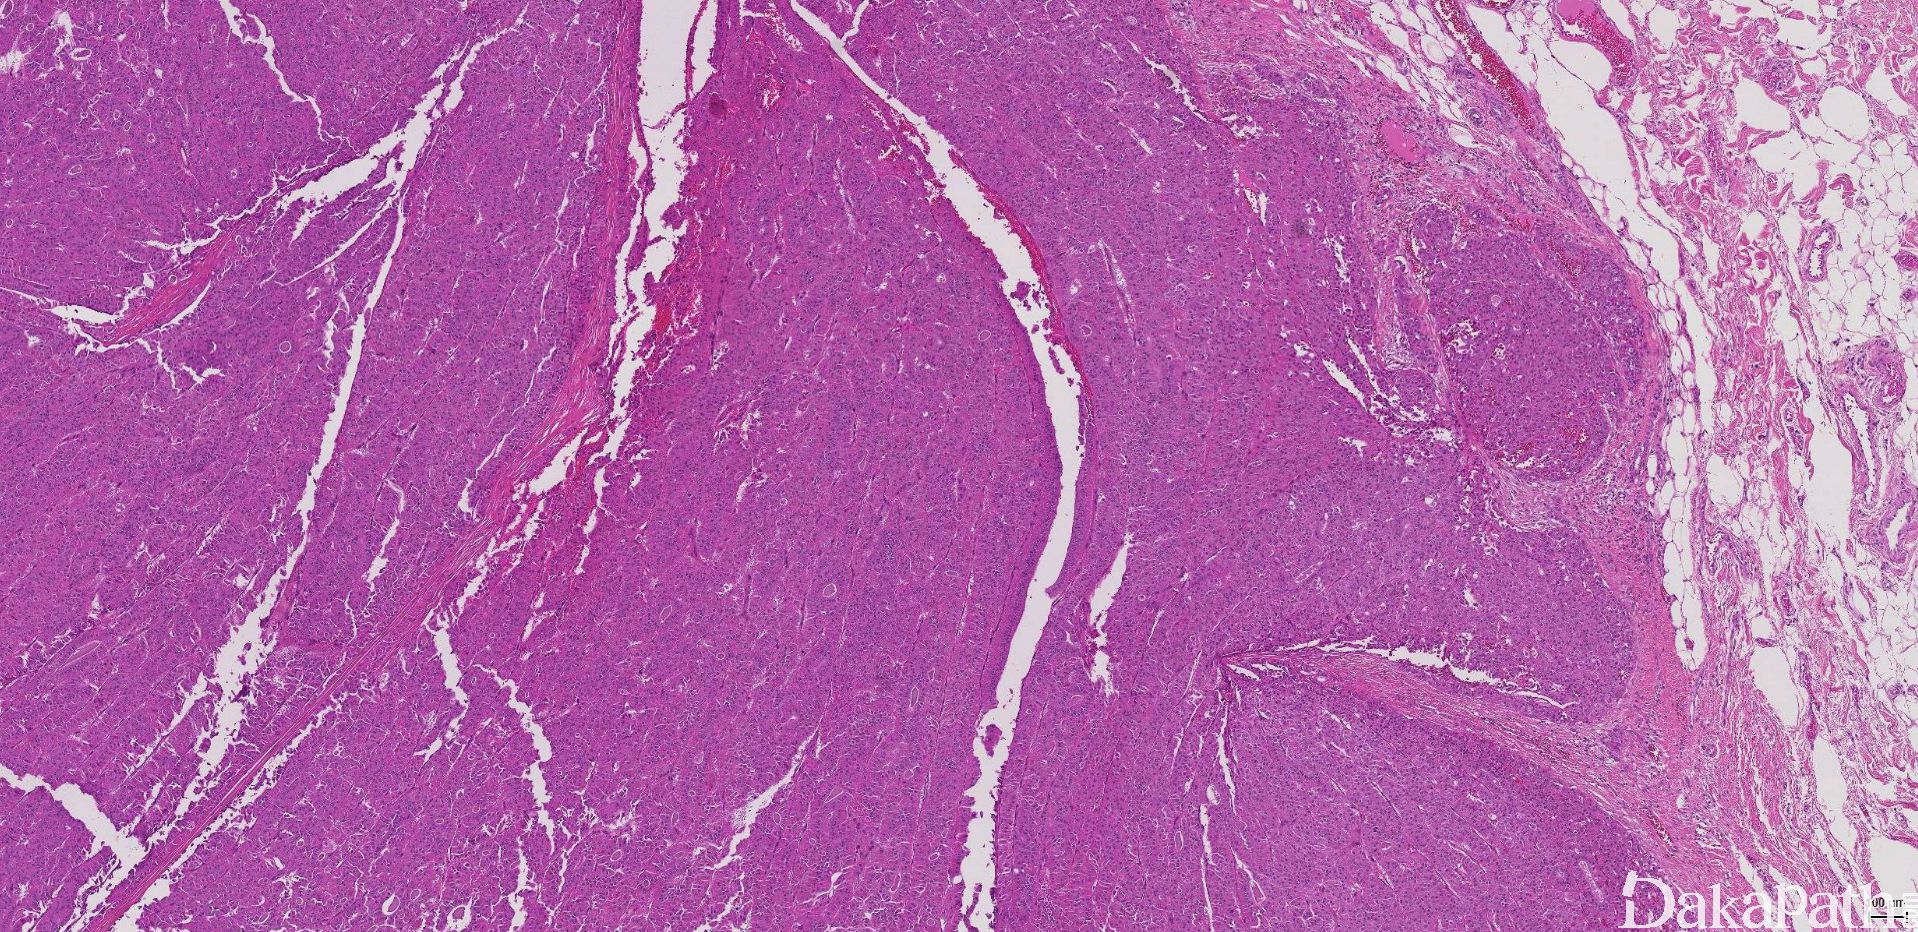

1. 有不同的形态特征,从分化很好的滤泡结构到实性和/或梁状结构;

2. 肿瘤细胞胞浆深嗜酸性颗粒状,细胞核浓染和多形,一般有显著的嗜酸性核仁;

5. 包膜和/血管侵犯是诊断的依据:

6. 包膜侵犯要求穿透纤维性包膜,包膜内细胞巢或索不作为包膜侵犯的依据;

7. 血管侵犯指包膜内或包膜外的血管侵犯;肿瘤细胞必须在血管腔内,且必须最少局部与血管壁相连,同时表面有内皮细胞覆盖或纤维素析出(或血栓形成)

8. 根据包膜侵犯的程度,滤泡性癌分为两个亚型:微小浸润和广泛浸润,但目前没有统一的诊断标准,有学者建议肉眼不能识别的包膜浸润为微小浸润,肉眼能识别的浸润为广泛浸润。